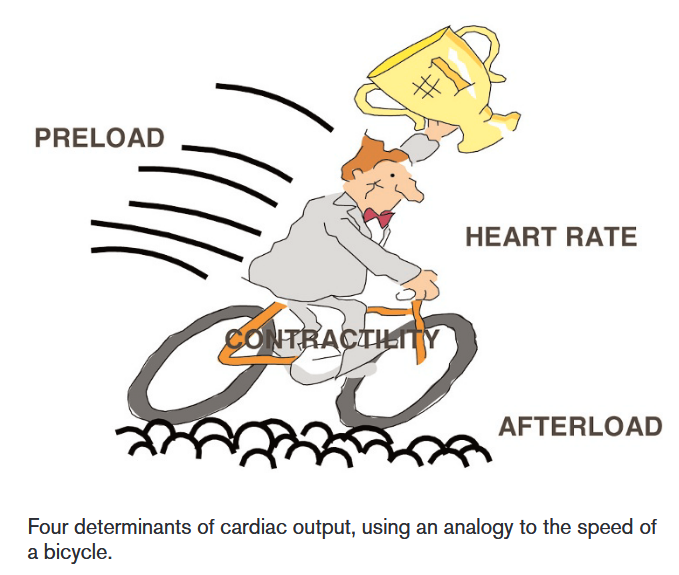

There are four determinants of cardiac output: Heart rate, contractility, preload and afterload, which can be understood through the analogy of a bicycle:

(Vincent, 2008)

(Vincent, 2008)

- The faster the heart beats, the more blood can be pumped out over a particular period of time.

- The harder the cyclist pushes on the pedals, the faster the bicycle will be, which can be equated to an increased contractility of the heart muscle.

- The preload, defined as the volume in the ventricles at the end of diastole, can be equated as the tailwind that allows the cyclist to move faster without any additional muscular effort, since the greater the stretch of myocardial cells, the greater the force of contraction will be.

- The afterload, defined as the resistance the heart must overcome to eject blood during systole, can be equated as the resistance of the road when cycling. The greater the afterload, the harder the heart must work to maintain the same cardiac output, leading to a decrease in cardiac output.